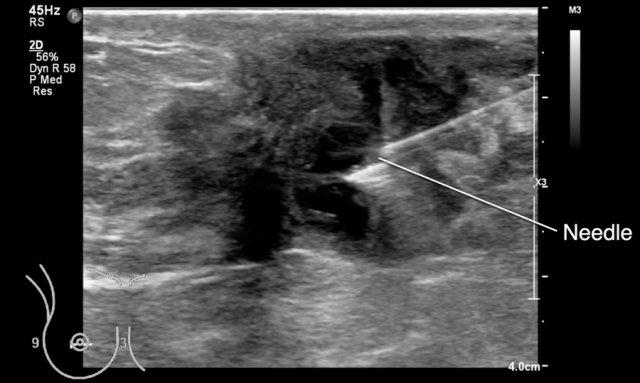

Hình ảnh siêu âm của một phụ nữ đến khám với triệu chứng sốt và khối đau ở vú phía sau núm vú bị thụt vào.

Trong quá trình ép và thả nhẹ bằng đầu dò, có thể quan sát thấy dịch trong ổ áp-xe di chuyển.

Cũng cần lưu ý hiện tượng tăng âm phía sau (posterior enhancement) — đây là dấu hiệu cho thấy cấu trúc này chứa dịch.

Tiếp tục xem hình ảnh tiếp theo…

Sau đó, ổ áp-xe được tiến hành chọc hút.

Chọc hút là phương pháp điều trị ưu tiên hàng đầu đối với áp-xe.

Trong trường hợp này không cần phẫu thuật hay kháng sinh, mặc dù đôi khi kháng sinh cũng được chỉ định kết hợp.

Đây là một ổ áp-xe khác nằm phía sau núm vú, đã được chọc hút.

Đây có thể là một thủ thuật gây đau cho bệnh nhân.

Tốt nhất nên tiêm thuốc gây tê tại chỗ vào da và tổ chức dưới da, sau đó cố gắng dẫn lưu mủ qua chính kim đó.

Nếu mủ quá đặc, cần sử dụng kim có kích thước lớn hơn.

Cần dành đủ thời gian để thuốc tê phát huy tác dụng.